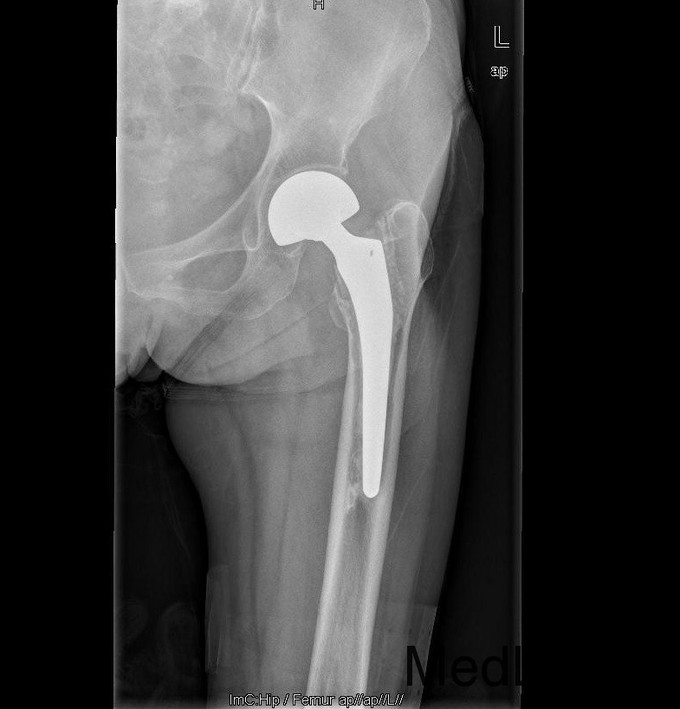

诊断:左双动股骨头置换术后假体松动、下沉、股骨骨缺损(PaproskyII型) 治疗:患者在全麻下左双动股骨头假体取出+同种异体骨植骨+左全髋关节翻修术,术后予以抗炎(二联)+抗凝+镇痛+护胃+补液等治疗,并予以抗骨质疏松药物

出院时左髋可屈曲90°,伸直0°,外展30° 讨论: 1、髋臼侧是否置换关键看什么? 2、Paprosky分型? 3、高龄患者行骨科大手术围手术期应着重注意哪些方面?( 体力、肺部感染、液体量与心功能、营养与饮食、锻炼与下肢深静脉血栓~~~~~) 4、假体柄的选择有何要求? 5、术后1天与术后3月的片子有何差别,试分析原因